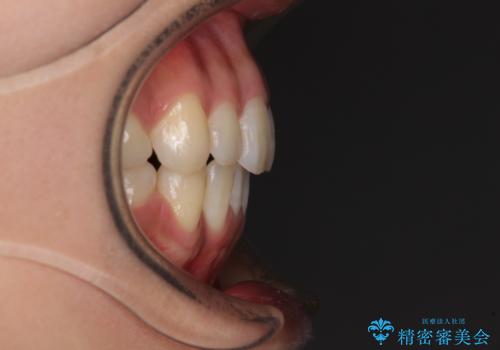

- 以前の矯正治療の後戻りにより、上下の前歯がでこぼこになってしまったことを気にして来院された患者様です。

口元がこれ以上突出することなく前歯の叢生が改善できるよう、歯と歯の間を削ってスペースを獲得し、インビザラインを用いて整えていくこととしました。

目安の装着時間である1日22時間をしっかりと実践してくださり、半年強という短期間で治療を終えることができました。